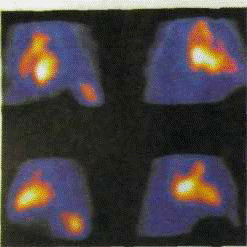

а — фаза диастолы; б — фаза систолы

Радионуклидная равновесная вентрикулография (РРВГ) проводится с использованием методики метки эритроцитов и vivo. После плотного разведения РФП в крови γ-камерой регистрируется несколько сотен изображений, на основе которых формируется единый усредненный образ сердечного цикла, сократительной функции сердца на протяжении нескольких сердечных циклов, визуализация изображения сердца в различные фазы. Основным показанием к проведению РРВГ являются ишемическая болезнь сердца, инфаркт миокарда, аневризма сердца, гипертоническая болезнь, диффузные поражения сердечной мышцы.